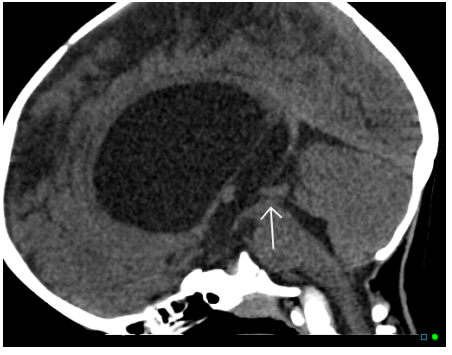

The arrow is pointing to part of the ventricular system which is narrowed.

Which part is this?

Cerebral aqueduct

Why is the fourth ventricle not dilated?

Because the obstruction is proximal to the 4th ventricle

How is this treated?

Tap and drain into abdomen via a ventriculo-peritoneal shunt.